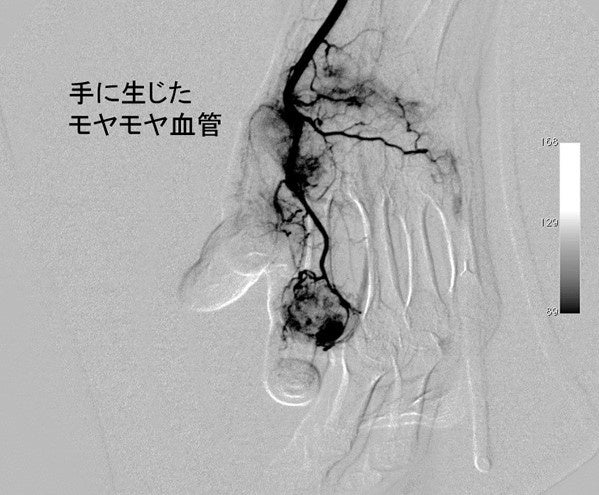

初めて聞いた原因でした。「モヤモヤ血管?!」って何??

今回の一番の驚きは、この「モヤモヤ血管」なるものの存在でした!!。

このモヤモヤ血管が血流異常を引き起こすことが「ヘバーデン結節」の主要因のようです。

だとすれば、このモヤモヤ血管がヘバーデン結節治療のターゲットになりますね。

モヤモヤ血管とは??

・モヤモヤ血管とは、痛みの原因部位にできる「異常血管」のこと。

・体内では「正常血管」以外に、病気の原因となる「異常血管」も作られる

・五十肩、ひざ痛、ヘバーデンなど治りにくい関節痛には異常な血管が存在する

”モヤモヤ血管”の命名由来は、いびつな構造でモヤモヤと見えることから名付けられたようです。